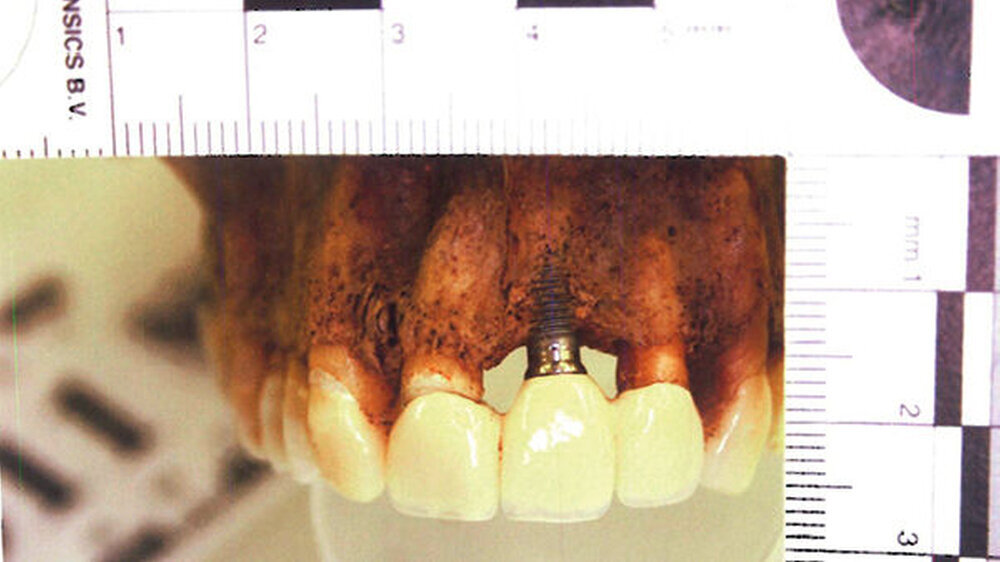

Zahnstatus:Aus dem Zahnstatus ersichtlich ist, dass es sich um hochwertige zahntechnische Arbeiten handelt, die auf eine mögliche privatkassenärztliche Versorgung schließen lassen. Der forensisch-odontologische Gutachter vermutet, dass alle Arbeiten durch denselben Zahnarzt gemacht wurden.

Neu:Inzwischen hat sich ergeben, dass es sich mit sehr hoher Wahrscheinlichkeit um XIFE-Implantate der Firma Densply Implants handelt.